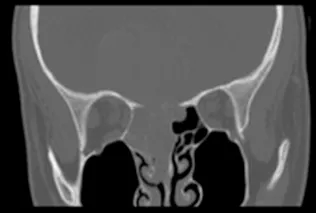

矢状缝早闭(Sagittal Craniosynostosis, SC)属于最常见的颅缝早闭类型...